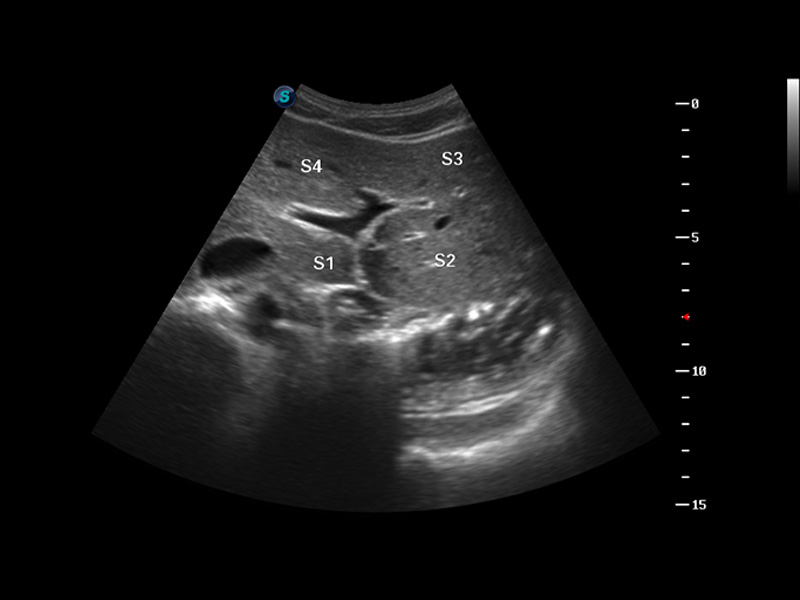

便携式彩色多普勒超声诊断仪

S8 EXP便携式彩色多普勒超声诊断仪是玖鼎集团研发的高端全身应用型便携彩超。高通道的VIS平台融合可视化(Visual)、智能化(Intelligent)和人性化(Smart)的特点,配以玖鼎集团自主研发生产的探头大家族,使您能够快速、准确的获得病人信息,提高工作效率的同时减轻疲劳。